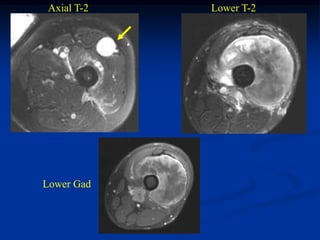

Case #259.2                   MFH with skip lesions

Axial T-2   Lower T-2

Lower Gad